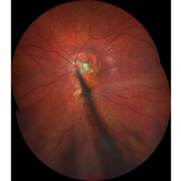

Nerve Stalk

Jun 18 2021 by Kristen Wagner

Fundus photograph of a hyperplastic primary vitreous, nerve stalk, and choroidal lesion of a 7-year-old male.

Photographer: Kristen Wagner, COT Tennessee Retina Nashville TN

Imaging device: Clarus

Condition/keywords: choroidal lesions, nerve, vitreous